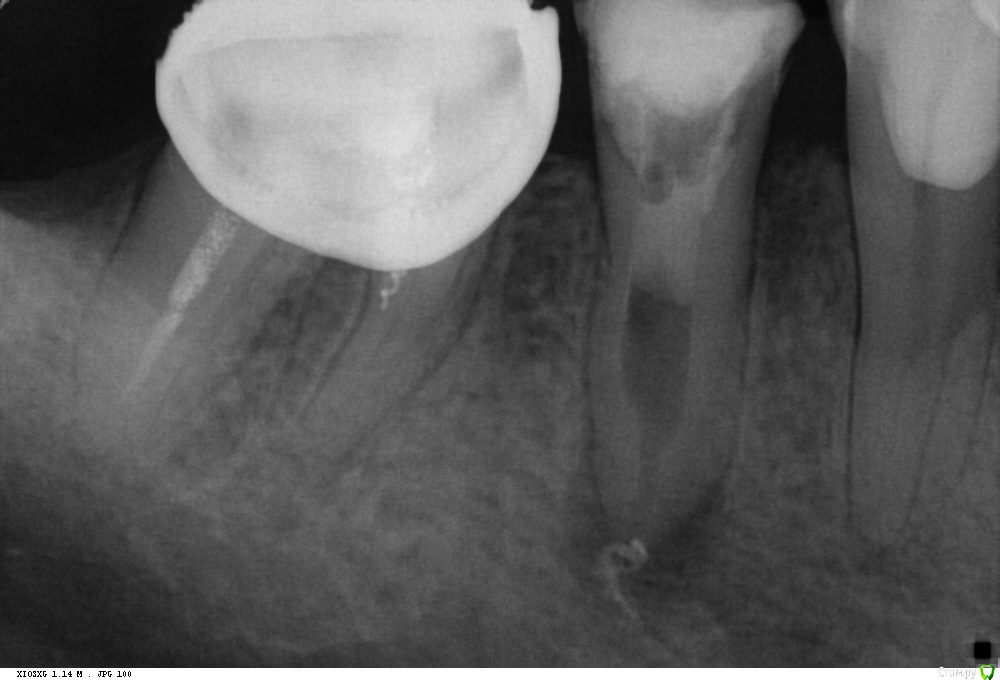

St. Опубликовано 13 октября, 2016 Поделиться Опубликовано 13 октября, 2016 История такова. Год назад зуб был с большой пломбой, но без периапикальных изменений на панораме. Никак себя не проявлял. 2-3 мес.назад со слов стал ныть, потом боль стала сильнее и проходила только от холодной воды. Тут вроде как ясно, классический гнойный пульпит. Болел ли тогда при накусывании пациент не помнит. Пошел к врачу, за 1 прием полечили каналы. На след.раз поставили постоянную пломбу. Через несколько дней пломба выпала. Поставили новую на стекловолокне. Боль вроде прошла.Сейчас появились боли при накусывании. Учитывая что до этого лечение было в гос и как минимум без коффа, решила перебрать. Не знаю, правильно ли?Но уже как есть. Достала СВЩ не очень удачно - истончила дист. стенку. Распломбировала. То что за апексом - скорее всего силлер( н-файлом не удится ничего). Получили экссудат. Сейчас на гидроокиси. У кого какие мысли как быть дальше? Собственно как лучше запломбировать и чем восстановить зуб после. Ссылка на комментарий

St. Опубликовано 14 октября, 2016 Автор Поделиться Опубликовано 14 октября, 2016 Феррул есть. Стенки все выше уровня десны. Ссылка на комментарий

krokomot Опубликовано 14 октября, 2016 Поделиться Опубликовано 14 октября, 2016 Перфы нет, трещины нет, можно понаблюдать, удалить никогда не поздно, тем более над врачом надо еще поиздеваться)) 1 Ссылка на комментарий

DmitrySH Опубликовано 14 октября, 2016 Поделиться Опубликовано 14 октября, 2016 Не преувеличивайте, удалять СВШ - рутинная процедура. Вы cosmopost когда- нибудь видели? Космопост - клевая штука )) СВШ с оптикой - рутина. Без оптики бывает тяжко. Перфы нет, трещины нет, можно понаблюдать, удалить никогда не поздно, тем более над врачом надо еще поиздеваться)) Если и издеваться, то апикально бы МТА, а далее адгезивно композитом, без всяких свш. Ссылка на комментарий